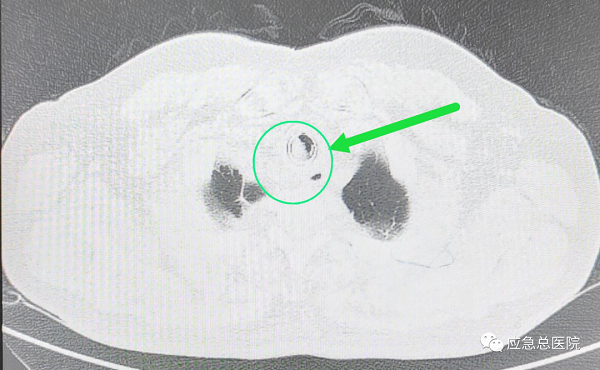

全身麻醉下,王洪武教授应用王氏插入法,仅5秒钟就成功插入硬质镜,建立了治疗和抢救通道,电子支气管镜下,可以看见原来的裸支架已经埋入气管粘膜内,突入的组织使得管腔仅有20%的空间能够流通空气,在张楠教授等专家的协助下,应用硬镜铲切、硬镜扩张、ND-YAG激光、高频电、氩气刀、二氧化碱冻取、球套扩张等多种技术配合,切除气管内增生的肉芽组织、部分异常粘膜,将原裸支架烧断、分解,抽丝剥茧,最后将整个支架完整取出,气管狭窄程度减轻为50%,手术结束后患者迅速苏醒,感到憋气症状明显缓解。